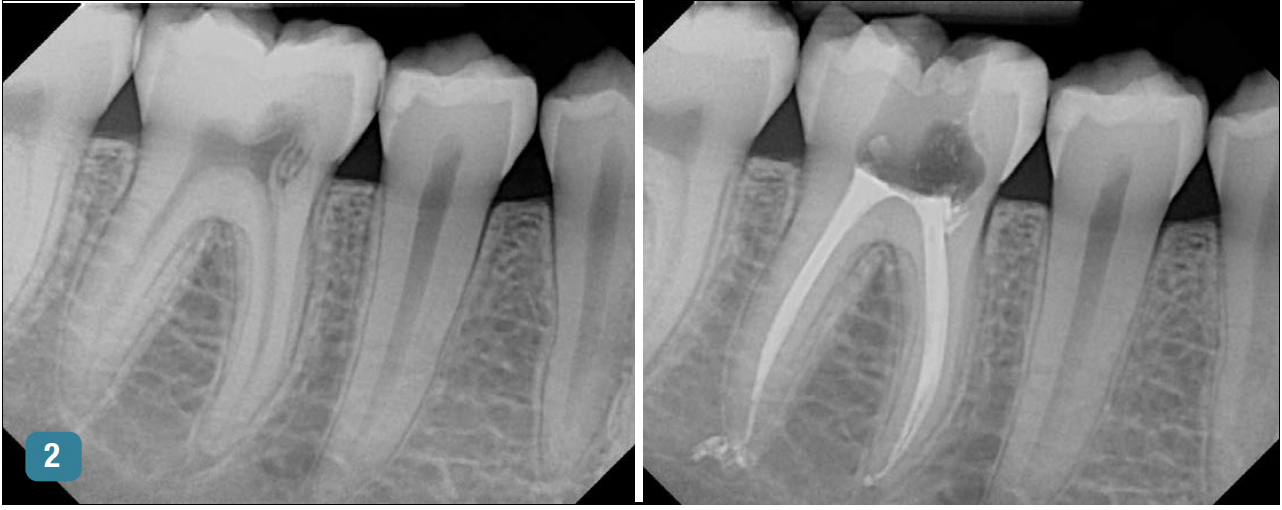

Figure 1 and Figure 2 provide examples of some cases that the author treated using the single-visit endo-restorative workflow. Despite the complex or challenging anatomy shown in these radiographs, the canals were able to be thoroughly irrigated by the multisonic irrigation system that was used with this workflow. For these cases, the one-day treatment workflow and the use of multisonic irrigation as described in this article enabled successful root canal treatment and improved patient satisfaction.

workflow). Fig 2, left panel: Preoperative radiograph of tooth No. 30 with internal inflammatory root resorption, a rare condition, resulting in acute periapical abscess in

another 20-year-old male patient with good dental and overall health. Fig 2, right panel: Postoperative radiograph (after the single-visit endo-restorative workflow).

Fig 2. Using the endo-restorative workflow described in this article, the complex anatomy shown in these radiographs was able to be irrigated by multisonic

irrigation. Fig 1, left panel: Preoperative radiograph of tooth No. 14 with acute periapical abscess and dental caries in a 20-year-old male patient with good dental

and overall health. A filling had broken, and the patient had postponed treatment. Fig 1, right panel: Postoperative radiograph (after the single-visit endo-restorative